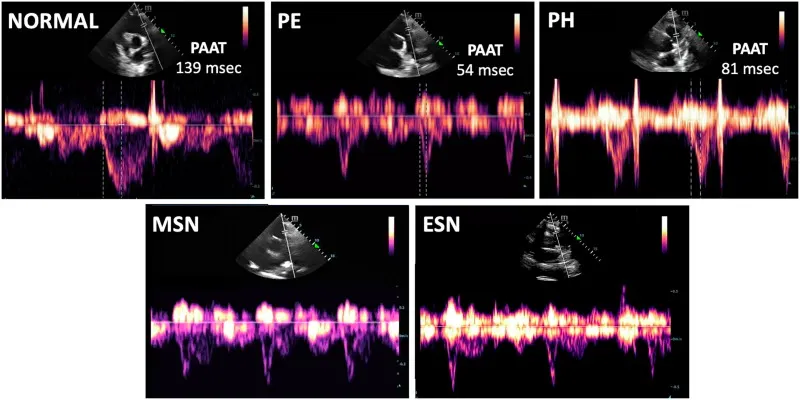

A4. Pulmonary artery acceleration time (PAAT)

PSX view, PV위치를 잡고, PV 위치에서 도플러 측정

≤ 60-80 msec suggests acute right ventricular dysfunction

< 105 msec suggests chronic right ventricular dysfunction

Image 6. (a, b, c, d, and e): Pulmonary artery systolic ejection waveforms.